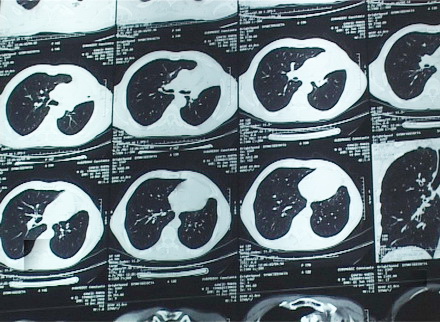

fumători! Cercetătorii vă avertizează că leziunile ce provoacă

teribilul cancer pulmonar apar imediat după ce vă aprindeţi prima

ţigară. Medicii sunt ingroziţi şi spun că pacienţii cu aceasta boală

ajung la ei în ultimul stadiu, când nu mai au cum să îi ajute.

Statisticile sunt sumbre: odata la trei zile, un constantean este

diagnosticat cu cancer pulmonar. Din pacate, boala nu are simptome

foarte evidente, astfel incat pacientii le pun pe seama altor afectiuni

si ajung la medic mult prea traziu. De multe ori, acestia nu mai au cum

sa ii ajute, pentru ca tratamentul este eficient

daca boala este depistata in primele faze.

Specialistii sunt ingroziti si spun ca varsta celor diagnosticati cu acest tip de cancer a scazut simtitor. Cel mai tanar constantean care a decedat din aceasta cauza avea numai 28 de ani si s-a apucat de fumat la numai 12. Omul a ajuns la medic in ultimul moment. Medicii vorbesc despre pericolul pe care il reprezinta tigara, inca din momentul in care este aprinsa. Leziunile la nivel genetic, ce induc riscuri de cancer, apar in doar cateva minute. Cancerul pulmonar provoaca la nivel mondial cele mai multe decese, cu peste 12 milioane de noi cazuri diagnosticate in fiecare an. Cercetatorii americani sustin ca 90 % dintre decesele de cancer pulmonar sunt in stransa legatura cu fumatul.